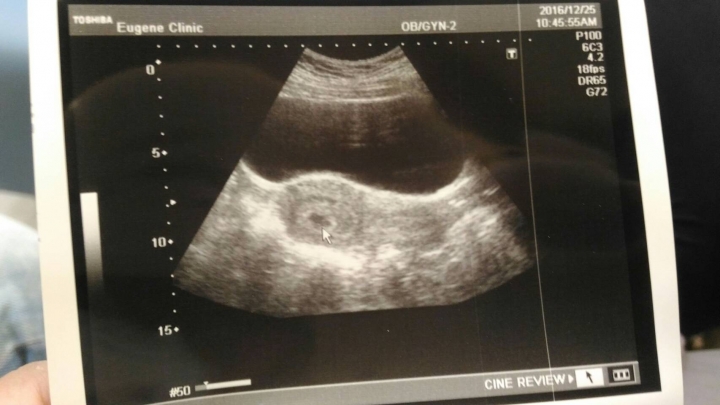

接著~我去兩間婦產科 第一間是圖二照的超音波~醫生照的很快 只有說五週大~1.6公分